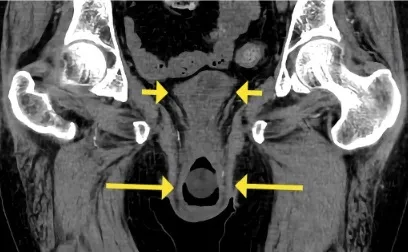

Caso clínico interessante para chamar nossa atenção para uma causa de IRA pós renal

Valkercyo Feitosa

3 anos atrás